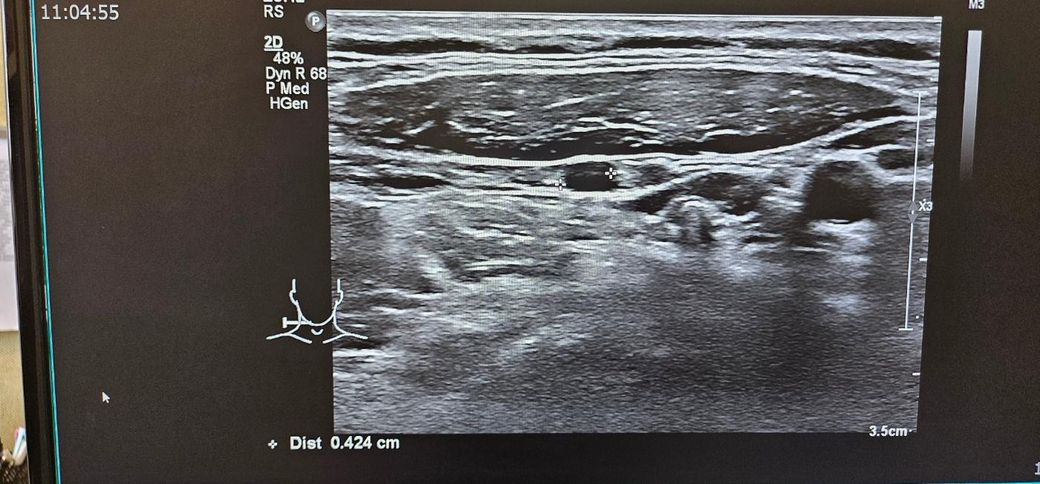

경부초음파 자세하게 설명좀 부탁드립니다

통증이있어서 초음파했는데

약먹고 통증은 없습니다

초음파 보시고 자세히 설명좀 부탁드립니다..

• 1번 째 사진

초음파는 검사를 한 사람이외는 잘 알 수가 없습니다.

판독지를 확인해보세요

아니면 판독지를 업로드해주세요